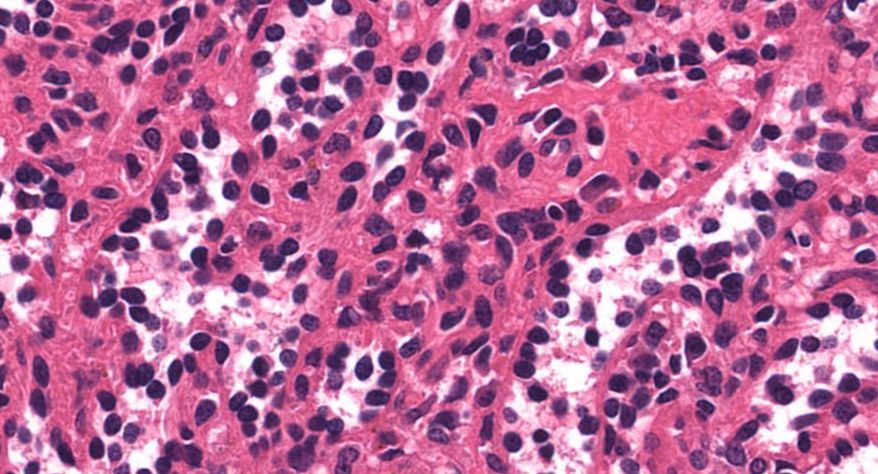

4 霍奇金淋巴瘤